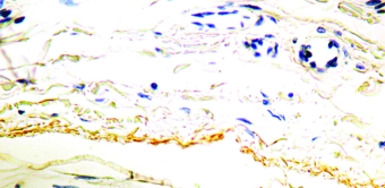

IHC-P analysis of human kidney tissue using GTX29519 Elastin antibody [BA-4].

WB, IHC-P, IHC